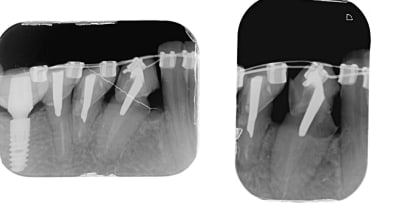

Et petit suivit d'un cas collé il y a sept semaine ( page deux sur ce fil ) .

Après deux semaines ça ne bougé pas trop donc je suis passé au niti 14 en bas il y a deux semaine et tout d'un coup c'est aller beaucoup mieux. En haut c'est toujours du niti 12.

Juste pour rappelle j'ai juste prit une empreinte alginate la patiente n'étant pas sure de l'option choisie ( céramique ou lingual ) et ai fait le labo sur deux jours.

Les 2D ça enfonce invisalign pour les cas simple que ce soit au niveau de la rapidité pour débuter le traitement , les cout labo ou l'expérience pour le patient.

7 semaine se sont écoulé depuis la pose des bagues. Ici si j'avais voulue faire de l'incognito ou du Win j'aurais due demandé une avance conséquente et prévoir limite deux mois pour recevoir le matériel. L'avance et/ou le délais d'attente ça rebute pas mal de patient.